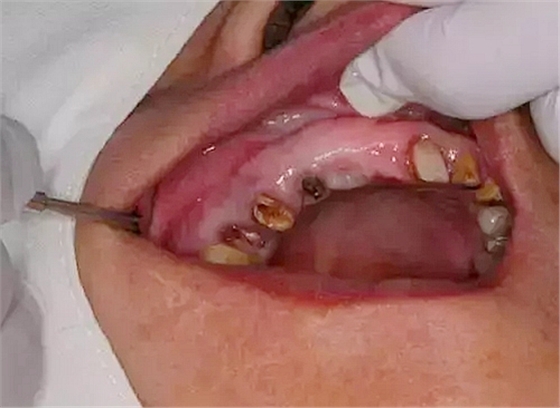

病例:患者,女、44歲,主訴:上頜烤瓷修復(fù)體脫落,要求重新烤瓷修復(fù)。

檢查:14根面旁穿,無法保留,15根長(zhǎng)不足。

處理:14、15微創(chuàng)拔牙+拔牙位點(diǎn)保存術(shù)。

?患者口腔內(nèi)部情況